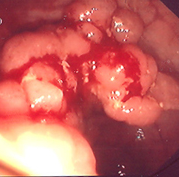

Κολονοσκόπηση που αποκαλύπτει πολυποειδή μάζα που προβάλλει στο μέσο τμήμα της αριστερής κολικής καμπής